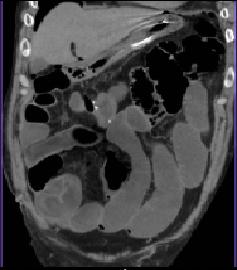

| Image TDM en coupe axiale : Invagination

ileo- colique |

La vue coronale

de TDM montrant la cause de l'invagination : Lipome

du grele de grand diametre